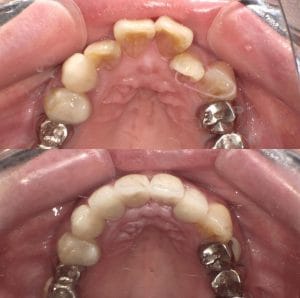

Case023

噛み合わせから審美的なところまで、トータルで治療させて頂いた患者様です。

ここまでやるとなると、できないクリニックもありますし、できるところでも年単位でかかってしまうクリニックが大半だと思いますが、今回は4月末にカウンセリングでご来院いただき、5月に治療をスタートして9月末には診療が終わっています。

治療回数や、治療期間がかかってしまうと、患者様も通院が辛くなったり疲れてしまったりしてしまうと思います。どんどん綺麗になっていく、食事がしやすくなっていくという実感がある方が患者様に楽しく治療に臨んでいただけると思うので、私は診療のスピード感を大切にしています。

トータルでやらせていただいたので、噛み合わせなどの機能面から外見などの審美性もかなり良くなり、患者様にも満足して頂けてよかったです。

治療期間 約4ヶ月